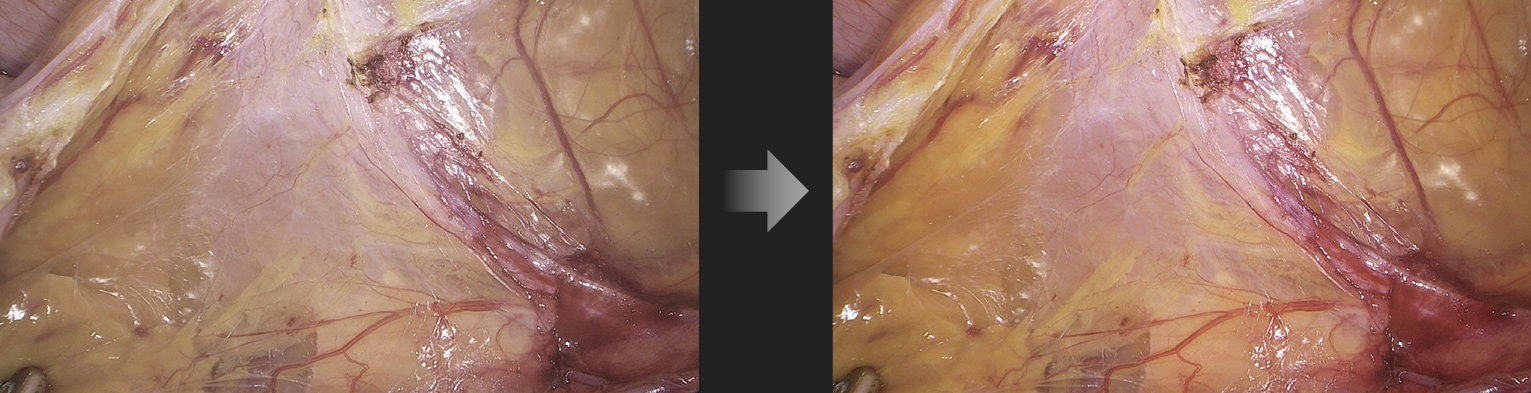

Intelligent Image Algorithm, Even in Extreme Circumstances

Intelligent Image Algorithm, Even in Extreme Circumstances

A variety of image post-processing algorithms make up for uneven lighting, local overexposure, thick fog etc., delivering clear, structured and layered images even in extreme scenarios.

Homogenous Brightness

Detail Enhancement

Color Enhancement

Before

After